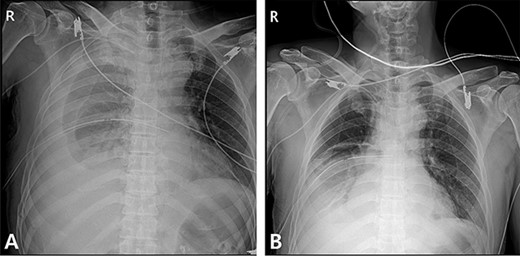

A 59-year-old man was admitted with multiple rib fractures and liver contusion due to a fall injury. He was standing on a chair for working at a farm, and it was knocked over causing him to fall and hit his flank against the corner of the chair. There was continuous pain while resting at the right flank and severe pain with pressure was noted, but no external wounds or bruises were observed. There were right 7th–11th rib fractures, scanty pneumothorax, minimal hemothorax and a 2-cm-sized liver contusion in abdomen and chest computed tomography (CT) scan (Fig. 1A, B). He was hospitalized for pain control and close observation in the general ward, and conservative management was initiated. Also, no significant changes were noted in the following daily follow-up chest radiographs. The patient suddenly complained of right-sided chest and back pain aggravation, cold sweating and fatigue 80 h after the traumatic injury. His mental status was alert, but v/s including systolic blood pressure (SBP) of 100–120 mmHg, heart rate (HR) of 40-60 beats/min and oxygen saturation of 100% during the admission changed to an SBP of 86/60 mmHg, HR of 88 beats/min and oxygen saturation of 97% when the symptoms occurred. Chest radiography was performed after the patient experienced aggravated symptoms, such as right-sided flank pain, cold sweating and fatigue. Compared to the previous scans, signs of increased opacification and peribronchial and parenchymal infiltrations were observed, which were indicative of hemothorax (Fig. 2A, B). We performed enhanced dynamic chest CT to identify any presence of active bleeding. On the chest CT scan, a large amount of hemothorax was identified in the right lung field along with multiple fractures of the right ribs. However, there were no signs of contrast leakage indicative of active bleeding (Fig. 3). Hemoglobin levels decreased from 13.1 g/dl on the day before the symptoms appeared to 11.5 g/dl at the onset of symptoms and to 9.4 g/dl after 2 h. Four packs of RBC transfusion and fluid were administered to the patient, and he was moved to the intensive care unit for close monitoring. And tube thoracostomy was performed, and 1600 ml of fresh blood was drained (Fig. 4A). The following day, 500 ml of blood was drained through the chest tube, but his v/s were stable (Fig. 4B). The amount of bleeding through the chest tube was decreased, but the drained fluid was fresh blood. And we thought that the remaining hematoma was not effectively drained, so the patient’s respiratory discomfort could persist and cause uneffective ventilation. And then we consulted with the Department of Thoracic Surgery, and video-assisted thoracoscopic surgery (VATS) exploratory thoracotomy was performed to identify the bleeding source caused by displaced rib and evacuate the large amount of hematoma. There was a large volume of hematoma within the pleural space and between the right lower lobe, diaphragm and fissure, but no active bleeding point was located. The fractured right 10th rib pierced through the pleural space and was displaced to the thoracic cavity, which was easily reduced. There was no injury surrounding the diaphragm, and although the general lung and chest wall contusions were severe, there were no signs of lung parenchymal lacerations (Fig. 5A–C). Chest tube drainage was serous, and there was no further bleeding. There were no signs of bleeding or any other abnormal findings on chest CT performed at the outpatient clinic, and the patient had no complaints of any symptoms (Fig. 6A, B).

Chest contrast-enhanced CT showed massive hemothorax with multiple rib fractures including 10th, 11th ribs (arrow) with no active extravasation of contrast.